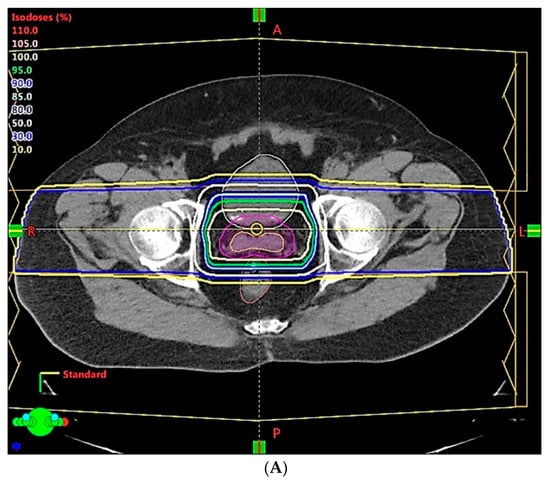

- Because of the inferior soft tissue contrast, orthogonal X-ray imaging systems rely on bony structures for verification of treatment position during patient setup. This type of setup technique can result in large positioning errors due to daily movement of the target and organs at risk (OARs) relative to the bony structures in the former technique. With fiducial markers implanted inside the prostate, many studies concluded that image registration by fiducial markers would reduce matching error. However, some patients may not accept marker implantation. Migration of markers with time may introduce registration errors. Such problems can now be minimized using on-board cone beam CT (CBCT). The better image quality of CBCT can provide 3D images and more information on the anatomic relationships between organs [64,65], which can be used to improve the accuracy of patient setup. Besides patient positioning, CBCT images can also provide information about inter-fractional changes in patient anatomy. In a recent study, an image-based correction method to generate pseudo-CT images from CBCT images was investigated for possible application in proton dose calculations [66] in adaptive PT. MRI, which has the ability to offer fast real-time imaging with high soft tissue contrast in the absence of ionizing radiation exposure [67], is being investigated for use in patient setup in RT. Our study using an external MRI setup room [68] and studies by others [69] indicated that patient positioning accuracy on the order of 1 mm is feasible, and is a significant reduction from that of conventional setup systems.